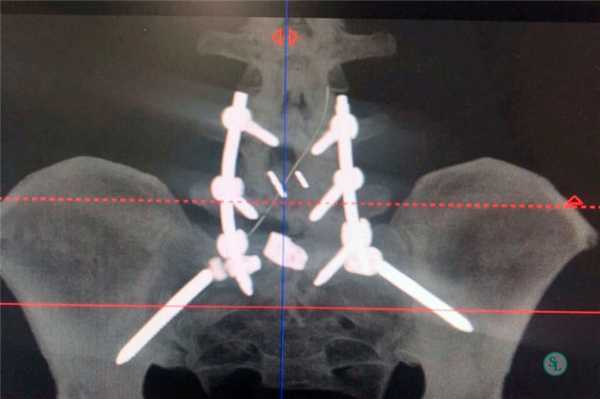

Рентгенограммы полученные после трансфораминального спондилодеза поясничного отдела позвоночника.

Транспедикулярная фиксация позвоночника

Транспедикулярная фиксация или ТПФ – операция, при которой позвонки фиксируются и стабилизируются при помощи специальных имплантов (транспедикулярных винтов). В каждом позвонке есть точка ввода винта, которую установил в 1985 году Рой Камилл — это точка пересечения поперечного отростка позвонка с верхнем суставным отростком. С помощью специальных инструментов в эту точку, вкручиваются винты определяя анатомически правильное расположение позвоночника, тем самым излечивая заболевание. Первые попытки установки имплантов были в 60–70 гг. прошлого века и с тех пор является «золотым стандартом» в лечения переломов и различных заболеваний позвоночника.

ТПФ выполняется под рентгеновским контролем, что позволяет хирургу точно контролировать каждое движение и избежать повреждения близкорасположенных анатомических структур. Чаще для этого используется ЭОП или КТ.